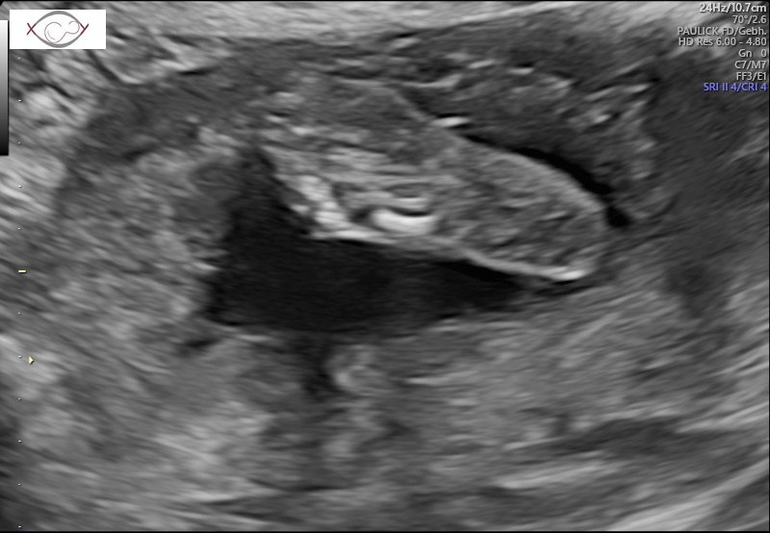

Рассматривали моего мальчишку сегодня вдоль и поперёк - крепыш, все органы как часики работают, 27 см и 554 гр мы уже😁☝️

Теперь я особо ничего уже не боюсь👍 2,5 недели назад писала пост о не полном предлежании плаценты, она за это время поднялась и уже 2,5 см от зева🤗Ура, ура, ура🥳🥳🥳 Особо беременной себя до сих пор не чувствую, в том плане, что ни отёков, ни какого то дискомфорта пока не ощущаю, но жду, готовлюсь морально🤪. Для папы нашего сделали фото писюна, чтобы уж точно он уже был уверен, что мальчик😅🤣🤣🤣 Пяточку, которой малой мне пиночки отвешивает и личико попытались сфоткать, но скромняшка всё ручками закрывался.